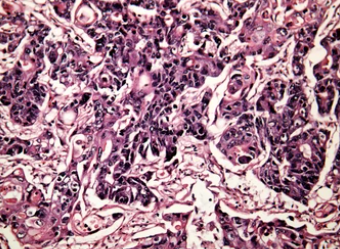

황달은 빌리루빈이라는 물질이 제대로 배출되지 못해서 발생하게 됩니다. 체내에 빌리루빈이 많이 쌓이게 되면 피부 및 눈 흰자위가 노랗게 변하게 되고 심하면 온몸이 노랗게 변하는 상태가 되기도 합니다. 주로 간경화나 간암 같은 질환들을 앓고 계신 분들에게 나타나는 증상이며, 다른 원인으로는 용혈성 빈혈, 패혈증, 췌장염, 담관염 같은 질병 역시 황달을 유발할 수 있습니다.